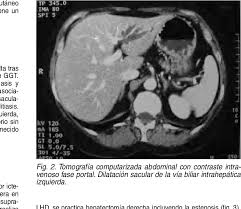

Sindrome De Caroli En Imagenes A Proposito De Un Caso

Sindrome De Caroli En Imagenes A Proposito De Un Caso from scielo.isciii.es. Para más información pulse aquí para ir al website.